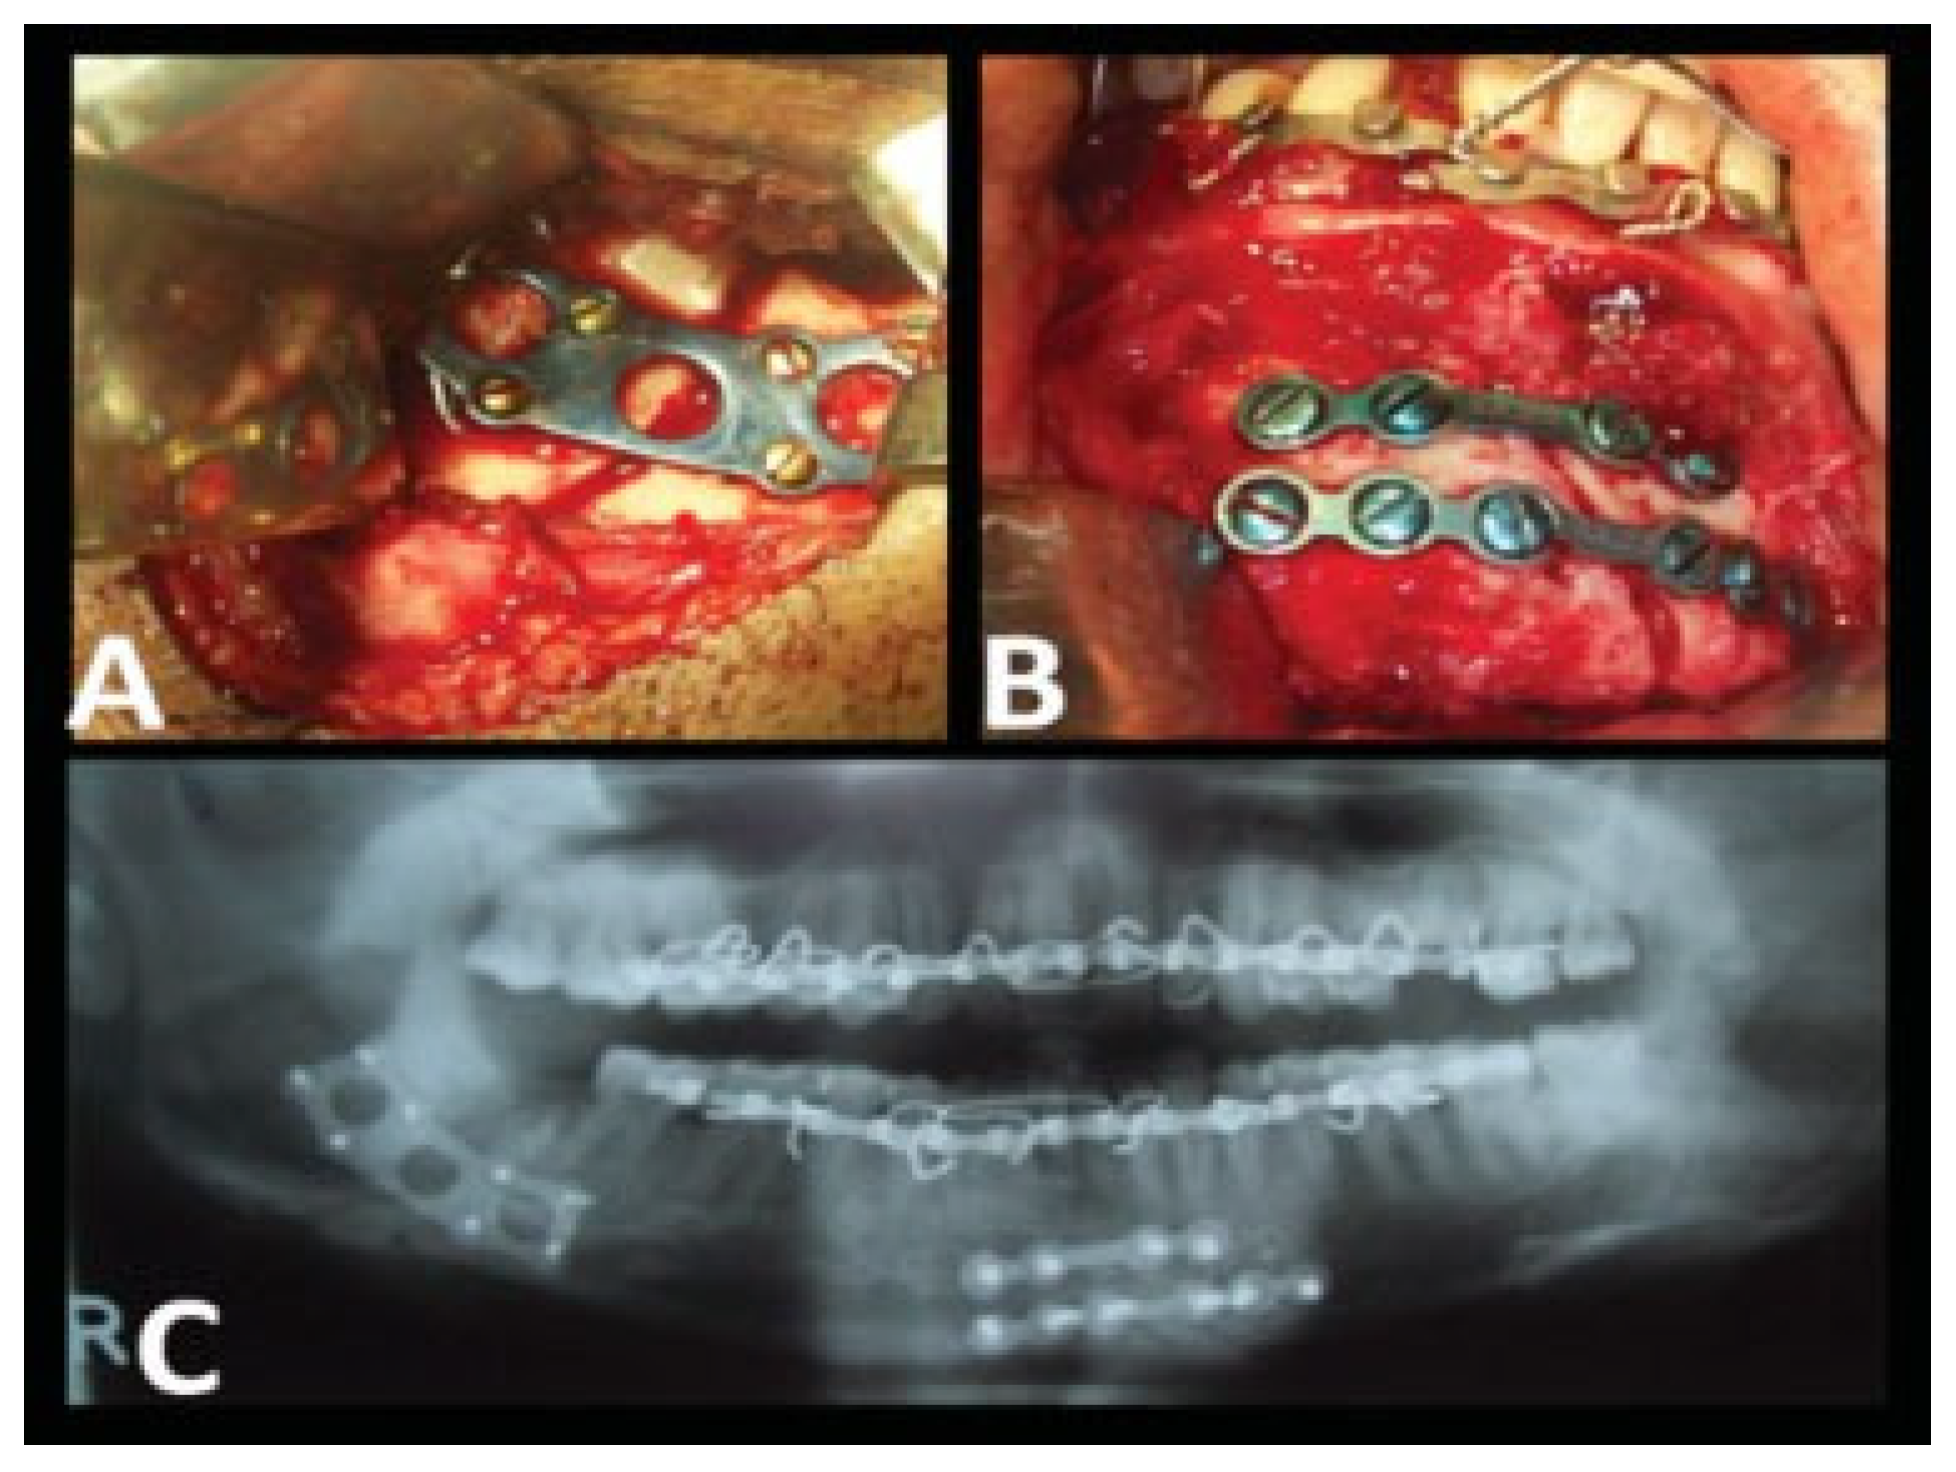

| Case no. | Fractured site | Technique | Postoperative MMF | Complications |

| 1 | Rt. parasymphysis and Lt. angle | ORIF | Not required | |

| 2 | Lt. angle | ORIF | Not required | |

| 3 | Rt. parasymphysis and Lt. angle | ORIF | Not required | Transient nerve dysfunction |

| 4 | Lt. angle | ORIF | Not required | |

| 5 | Lt. angle | ORIF | Not required | |

| 6 | Lt. body and Rt. angle | ORIF | Not required | Infection |

| 7 | Lt. angle | ORIF | Not required | |

| 8 | Lt. parasymphysis and Rt. angle | ORIF | Not required | |

| 9 | Lt. parasymphysis and Rt. angle | ORIF | Not required | |

| 10 | Rt. angle | ORIF | Not required | Transient nerve dysfunction |

| 11 | Rt. angle | ORIF | Not required | |

| 12 | Lt. angle | ORIF | Not required | |

| 13 | Rt. parasymphysis and Lt. angle | ORIF | Not required | |

| 14 | B/l angle | ORIF | Not required | |

| 15 | Lt. parasymphysis and Rt. angle | ORIF | Not required | Infection |

| 16 | Rt. parasymphysis and Lt. angle | ORIF | Not required | |

| 17 | Lt. angle | ORIF | Not required | |

| 18 | Lt. angle | ORIF | Not required | Transient nerve dysfunction |

| 19 | Rt. angle | ORIF | Not required | |

| 20 | Lt. parasymphysis and Rt. angle | ORIF | Not required |